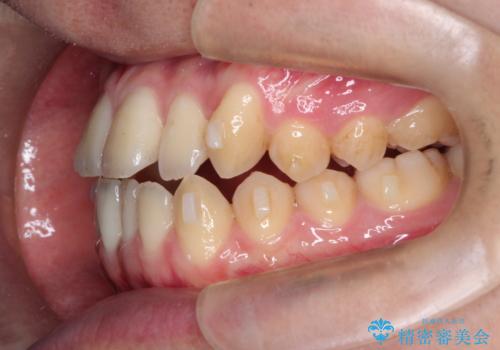

前歯のデコボコ インビザラインによる目立たない矯正

- 前歯のデコボコを主訴に来院された患者様です。

目立たないそうちをご希望されたので、インビザラインにて治療することとしました。

歯と歯の間をわずかに削ってスペースをつくり、デコボコを改善しました。